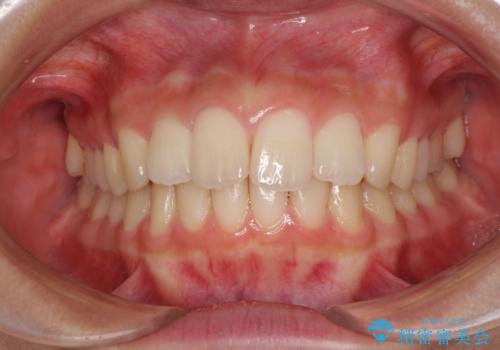

就職前にきれいな歯並びにしたい 大学生のインビザライン矯正

- 就職するまでに歯並びをきれいにしたいとのことで来院された患者様です。

前歯の叢生を気にしていましたが、極力突出感を改善できるようにすることとし、インビザラインにて矯正治療を行うこととしました。

改善の期待できない口元の突出感改善を希望されたため、いたずらに治療期間が延びましたが、きっちりと仕上がりました。